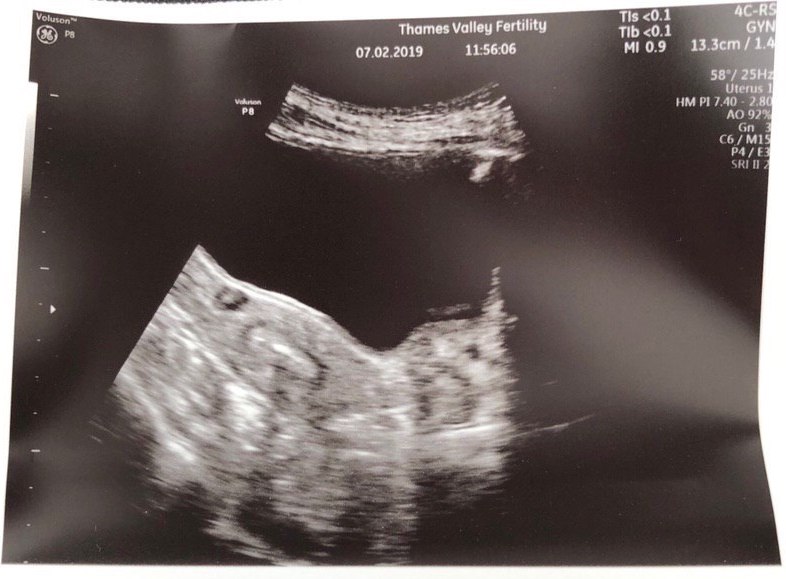

On Feb 7th at 11:30am, the implantation happens. If you have no idea what you’re looking at in the picture above, here are some info to orientate your eyes: